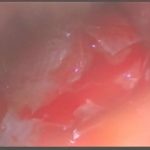

術中写真

摘出 前